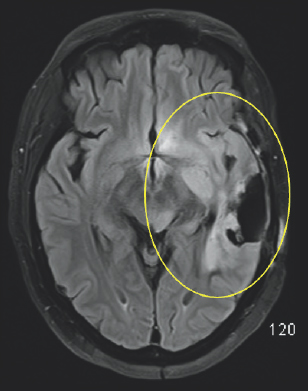

White and light gray color variations are enclosed by a black and dark gray outline. There is significant white coloration on the right side of the image which is highlighted by a yellow oval.

FIGURE 2.6 Brain MRI after surgery. There is surrounding signal alteration on the MRI sequence image similar to the MRI before the surgery, which is nonspecific but likely represents swelling (yellow oval).

Initially, after the treatment, there was no obvious progression in his symptoms, but by mid-May of that same year, there was a dramatic decline in his condition (Fig. 2.4–2.7). Several concerning transient symptoms appeared, including confusion, lethargy, and significant memory loss, which impacted his compliance with his treatments and caused him to sometimes forget his regimen.